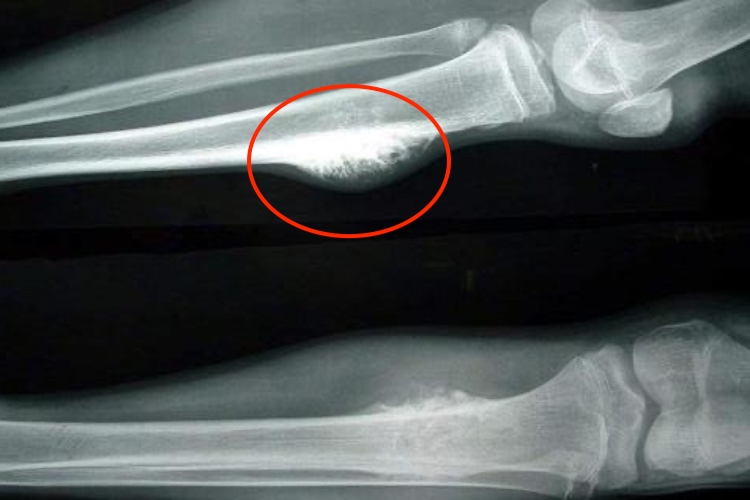

骨癌的早期小肿块表现为骨的表面出现一个较硬的肿块,可伴有疼痛,病因不明,需手术联合化疗、放疗治疗。

骨癌的早期小肿块表现为患处有一肿块,局部肿胀、疼痛,多为持续性,逐渐加重,夜间尤重,邻近关节功能障碍。局部表面皮温升高,静脉怒张。还可伴有疲劳、发热以及消瘦等全身症状。